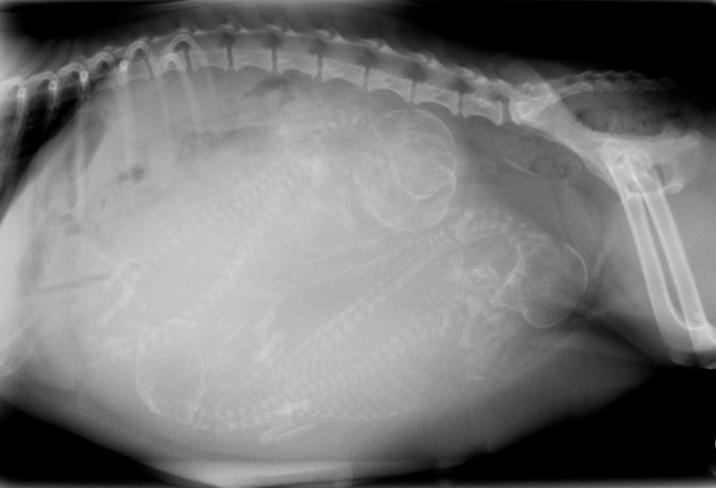

Antes de explicar se é normal uma cadela sangrar após o parto, devemos saber o que acontece com o corpo dela durante esse período. O útero da cadela é em forma de Y com um chifre uterino de cada lado onde os filhotes serão alojados. Portanto, a primeira mudança considerável será um aumento no tamanho do útero, que expandirá gradualmente à medida que os filhotes crescem. Além disso, o útero irá concentrar uma quantidade maior de sangue para manter os fetos nutridos e garantir o seu bem-estar. Às vezes o parto natural não é possível e estamos diante de uma cesárea ou uma concepção indesejada. Por esse motivo uma cirurgia uterina, como uma ovariohisterectomia, pode ter o sangramento como uma das complicações a serem consideradas. Outra mudança importante ocorre nas mamas, que escurecem e aumentam em preparação para a amamentação. Todas essas modificações são induzidas por hormônios.

Durante o parto, que ocorre por volta dos 63 dias de gestação, o útero se contrai para expulsar os filhotes ao exterior. Cada um deles é envolto em uma bolsa cheia de líquido amniótico e preso à placenta pelo cordão umbilical. Para nascer, a placenta deve ser separada do útero. Às vezes, a bolsa se rompe antes de sair o filhote, mas é comum que ele nasça com a bolsa intacta e será a mãe quem a romperá com os dentes. Ela também morderá o cordão umbilical e, normalmente, come os restos mortais. A separação das placentas do útero produz uma ferida, que é o que explica por que é normal a cadela sangrar após o nascimento. Então, se a sua cadela deu à luz e sangra, você deve saber que é uma situação normal.